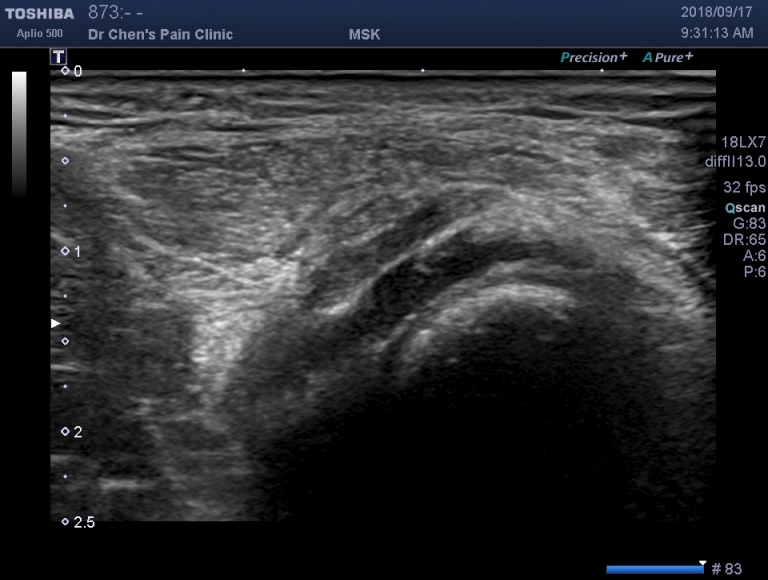

超音波診斷:肌肉裂傷

在超音波底下可以清楚地看到肌肉裂傷